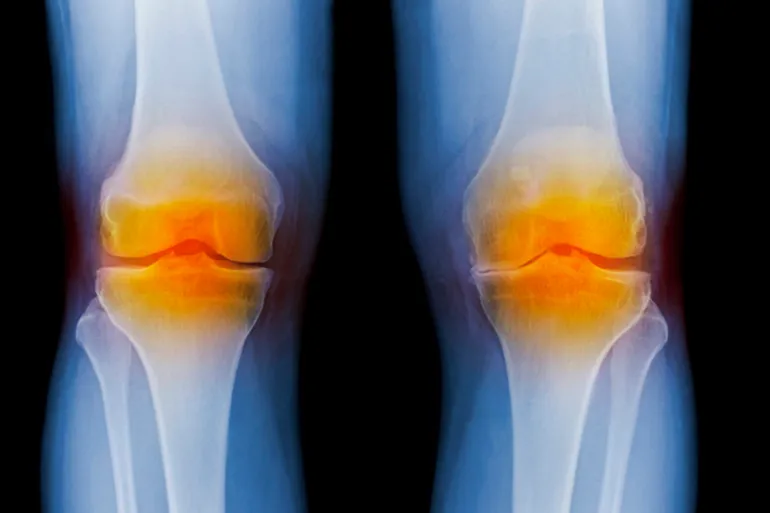

تحدث خشونة الركبة عندما يتآكل الغضروف في مفصل الركبة، فتحتكّ العظام بمفصل الركبة مما يتسبب في احتكاك يؤدي إلى إصابة ركبتيك بألم أو تصلب أو تورم، وهي حالة شائعة جدا، فما يقرب من 46% من الناس سوف يصابون به خلال حياتهم، وفق كليفلاند كلينيك.

وخشونة الركبة مصطلح عام، غير علمي، يشير إلى إصابة الركبة بمرض الفصال العظمي (Osteoarthritis).

أما الاسم العلمي الأدق الذي يصف خشونة الركبة فهو مرض الفصال العظمي في الركبة (Osteoarthritis of the knee).